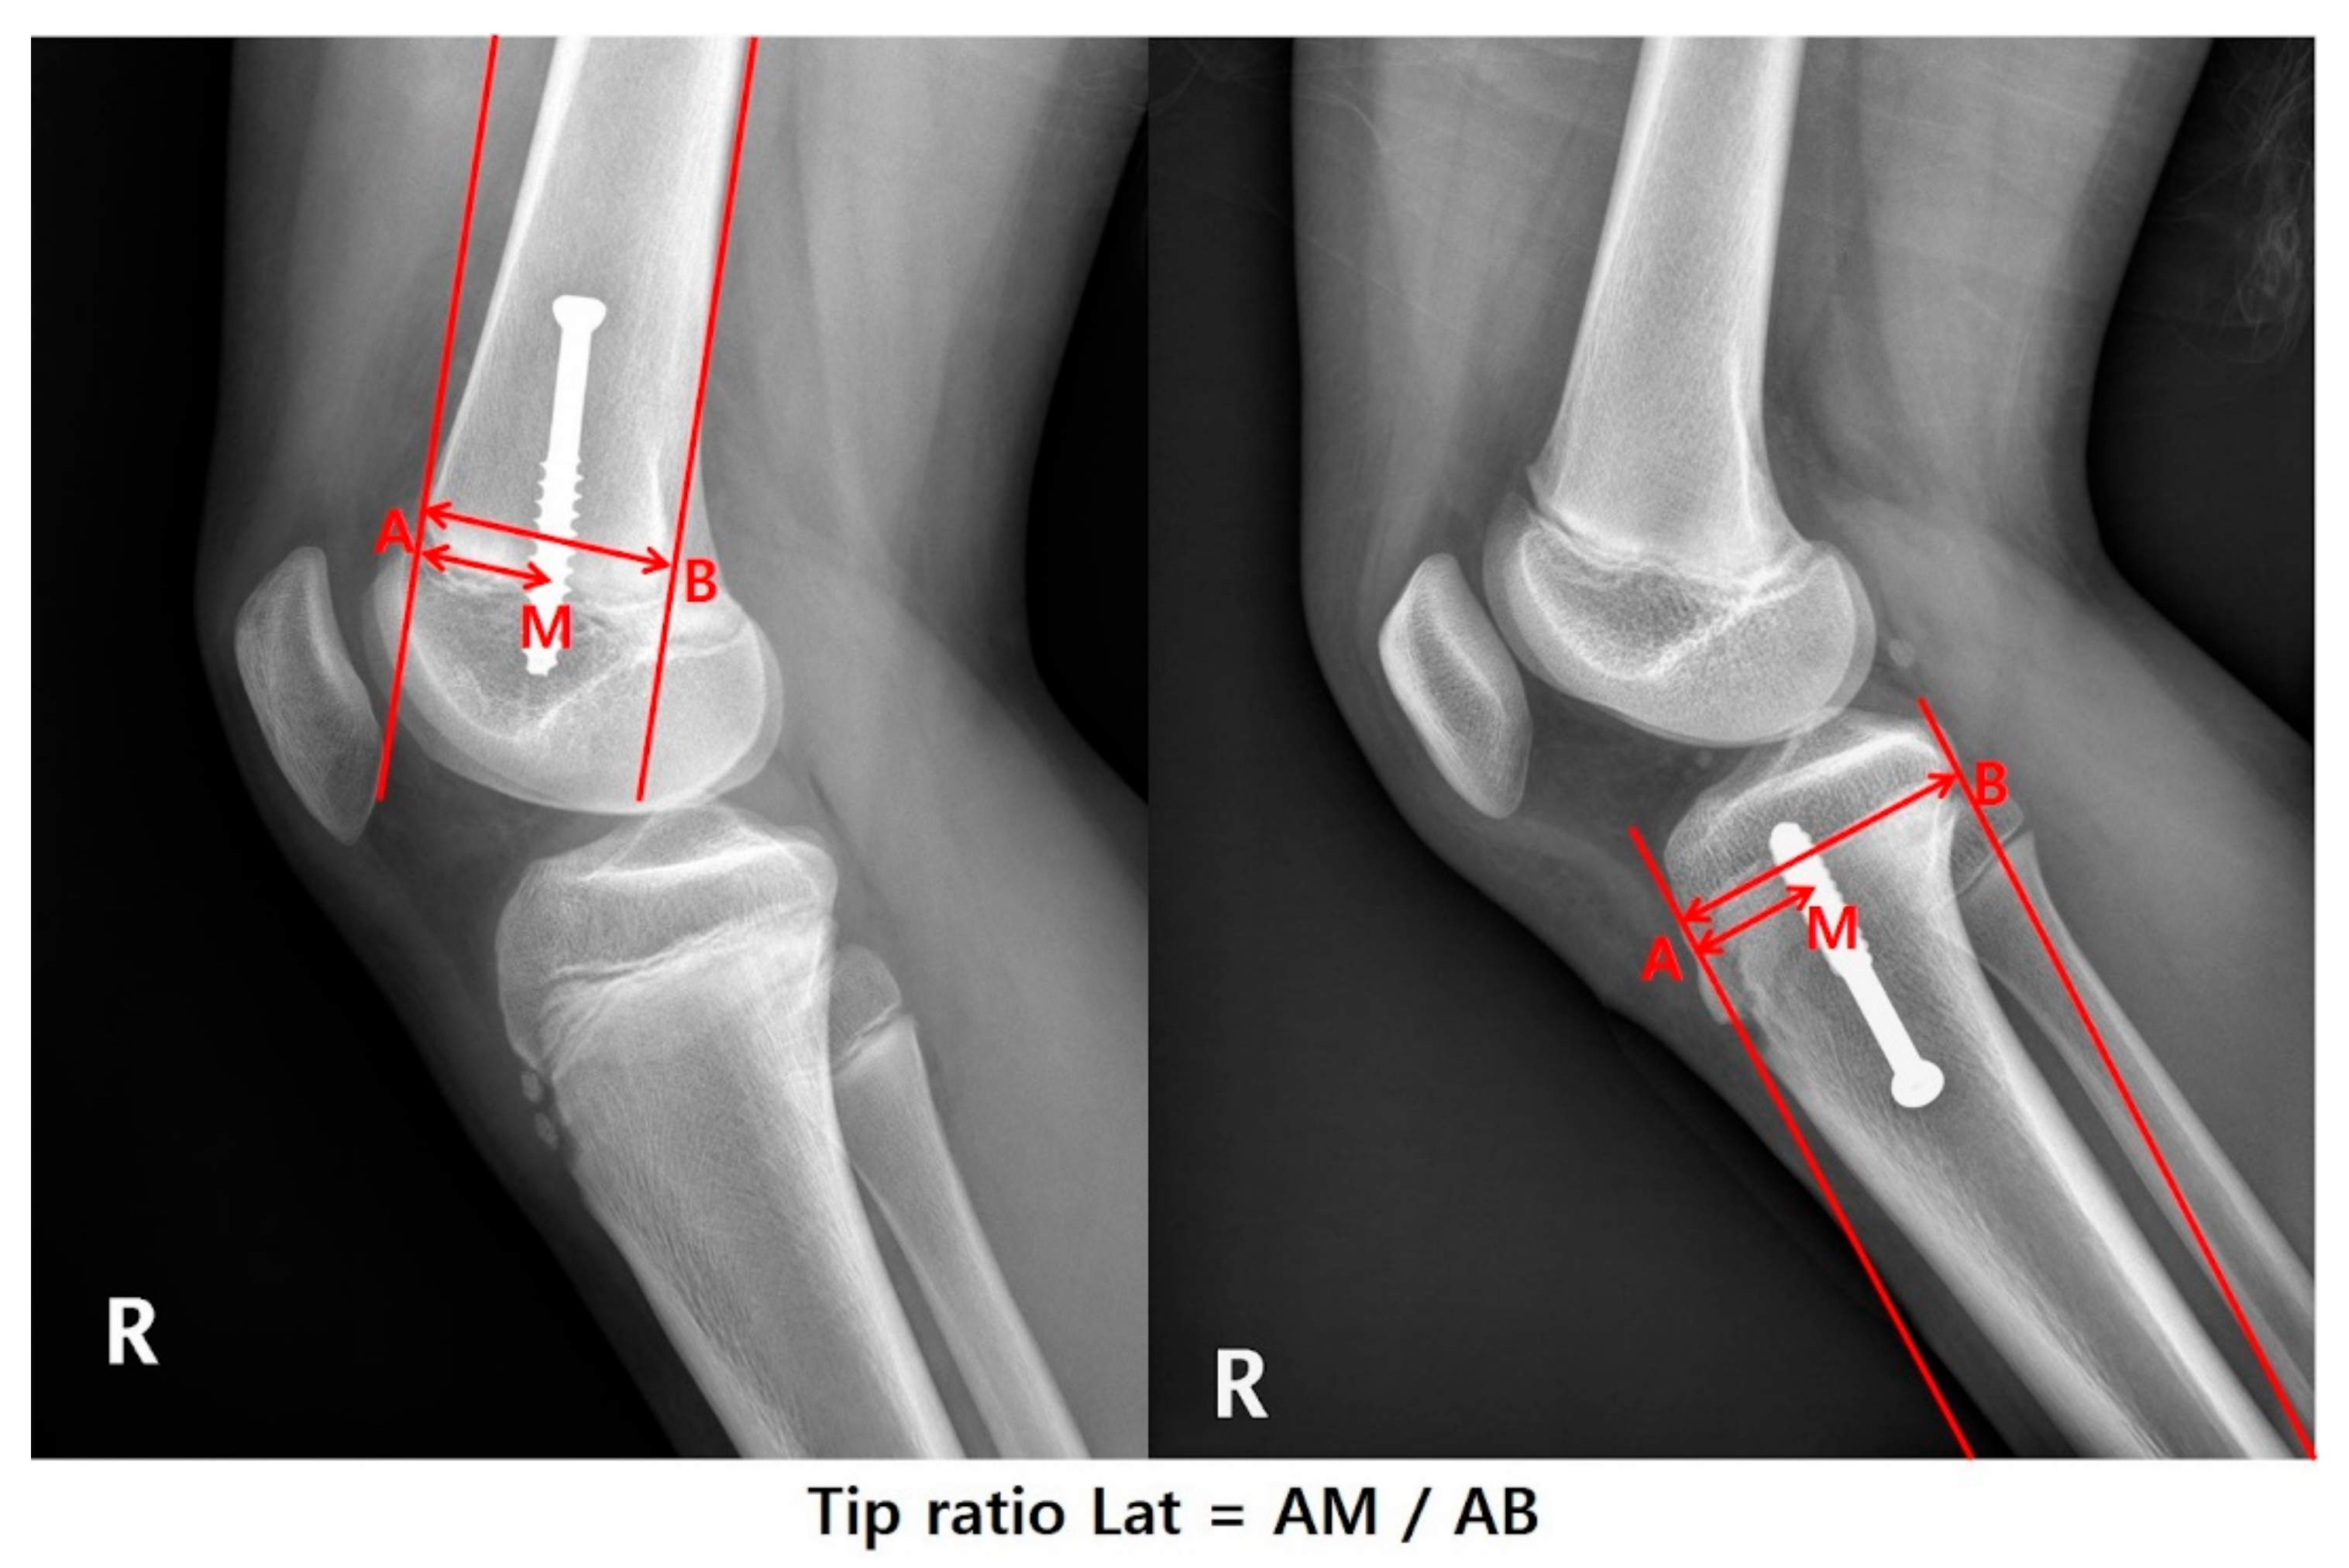

| Tip ratio Lat | 0.45 (0.39–0.5) | 0.41 (0.37–0.48) | 0.5 (0.47–0.54) | <0.001 |

| Tip ratio Lat | −1.313 (−2.250 to −0.377) | −0.329 | 0.008 | |||

| Tip ratio Lat | −2.767 (−7.460 to 1.926) | −0.145 | 0.252 | |||

| ** Tip ratio Lat | Valgus | −0.203 (−1.740 to 1.333) | −0.040 | 0.797 | |||

| Varus | −1.543 (−2.507 to −0.58) | −0.595 | 0.006 | −1.218 (−2.107 to −0.33) | −0.470 | 0.016 | |

| ** Tip ratio Lat | Valgus | 3.059 (−4.684 to 10.802) | 0.119 | 0.443 | |||

| Varus | −6.750 (−11.838 to −1.662) | −0.523 | 0.018 | −4.238 (−8.828 to 0.352) | −0.328 | 0.090 | |